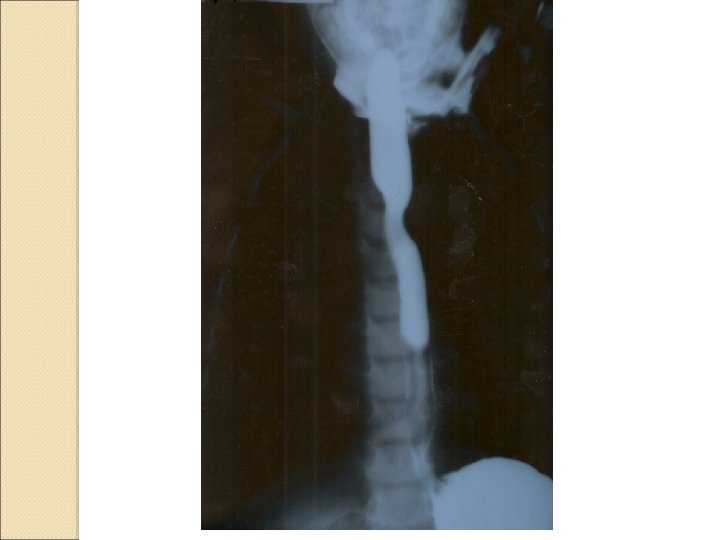

Yabancı cisim aspirasyonu

Laboratory findings Most infants with a single episode of wheezing will not require a chest radiograph, other than to confirm positive additional findings and/or to alleviate parental anxieties Any child with recurrent episodes of wheezing or congenital anomalies should have anteroposterior and lateral radiographic views taken to ascertain the presence of hyperinflation and/or structural abnormalities Suspicion of structural abnormalities may warrant additional imaging studies such as a CT or MRI and/or direct visualization using laryngobronchoscopy